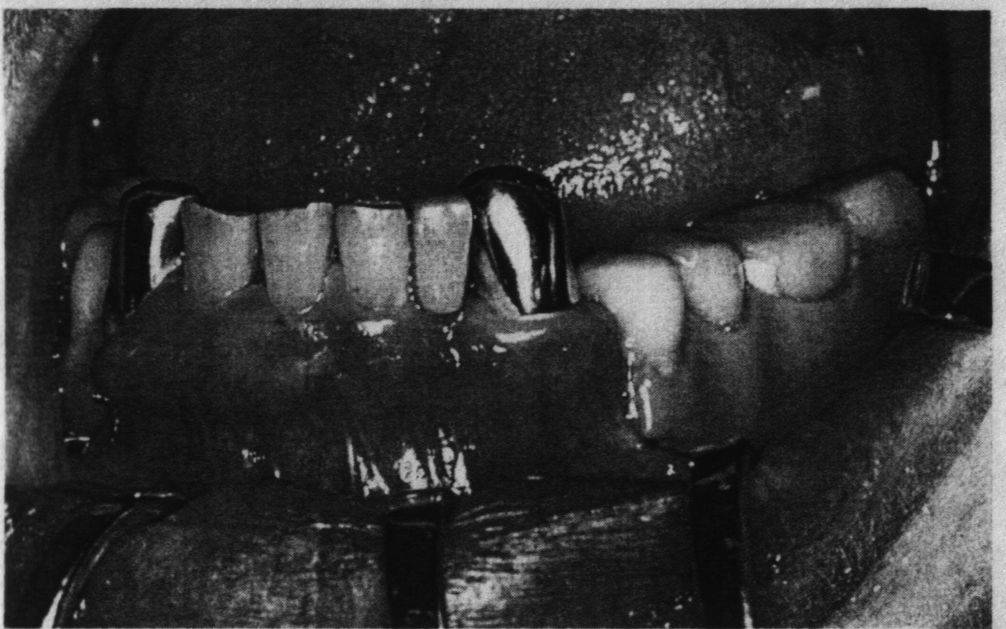

Не менее важны эстетические качества мостовидных nпротезов. Все чаще встречаются пациенты, не желающие иметь видимые при улыбке nили разговоре металлические детали протеза. Наилучшими в этом отношении nсчитаются металлокерамические конструкции.

С точки зрения гигиены к мостовидным протезам nпредъявляются особые требования. Здесь большое значение имеет форма промежуточной nчасти протеза и ее отношение к окружающим тканям протезного ложа слизистой nоболочки альвеолярного отростка, десне опорных зубов, слизистой оболочке губ, nщек, языка. В переднем и боковом отделах зубной дуги промежуточной части nнеодинаково. Если в переднем отделе она должна касаться слизистой оболочки без nдавления на нее (касательная форма), то в боковом отделе между телом протеза и nслизистой оболочкой, покрывающей беззубый альвеолярный отросток, должно nоставаться свободное пространство, не препятствующее прохождению разжевываемых nпищевых продуктов (промывное пространство).

При касательной форме отсутствие давления на слизистую nоболочку проверяется зондом. Если кончик его легко вводится под тело протеза, nзначит, давление на десну отсутствует, и в то же время нет видимой щели, nкоторая не эстетично выглядит при улыбке или разговоре.

В боковом отделе зубного ряда, создавая промывное nпространство, стремятся избежать задержания пищи под промежуточной частью nпротеза, что может вызвать хроническое воспаление этого участка слизистой nоболочки. Именно поэтому промывное пространство делают достаточно большим, особенно nна нижней челюсти. На верхней челюсти с учетом степени обнажения боковых зубов nпри улыбке, промывное пространство делают чуть меньше, чем на нижней, а в nобласти премоляров и клыков, открывающихся при nулыбке, оно может быть сведено к минимуму, вплоть до касания слизистой nоболочки. В каждом конкретном случае этот вопрос решается индивидуально.